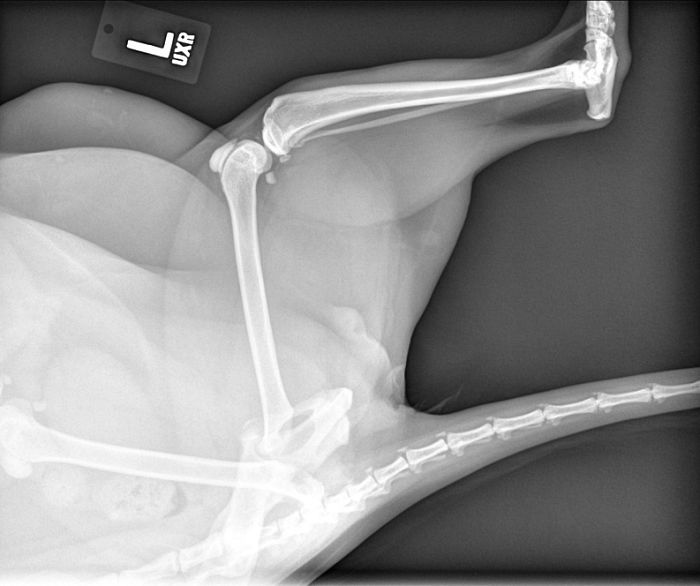

Went Through 21 Years Thinking I Never Broke A Bone Until An X-Ray For A Shoulder Problem Revealed This Atrocity, It Broke And Healed Without Me Knowing, Was Nice Knowing You

It could happened when he/she was a baby. You'd think you'd notice but if it happens at birth, it can easily be missed